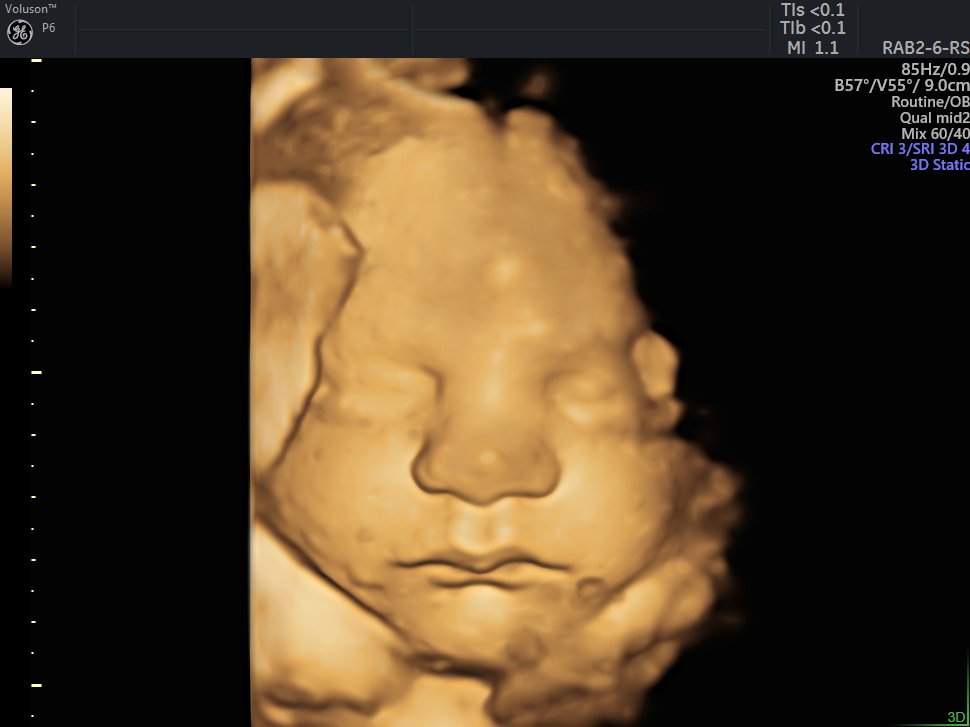

4 Boyutlu (Renkli) Ultrason ve Doppler Ultrasonografi

4 D Ultrasonografi